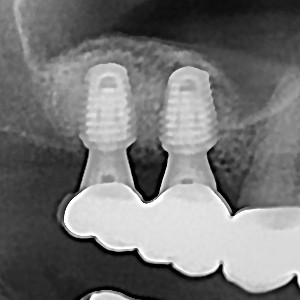

임플란트 뼈이식 + 임플란트

448e75263793fe92c7be216679361f49_1767847057_1604.jpg